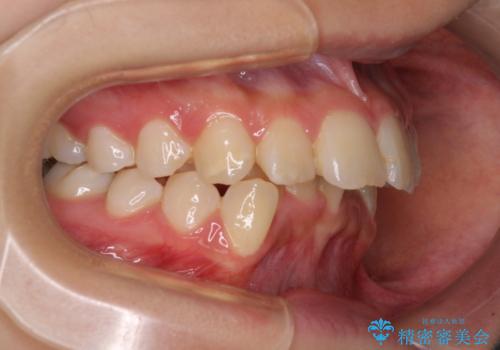

抜歯矯正により、口元の印象だけでなく、横顔の印象も大きく改善されました。